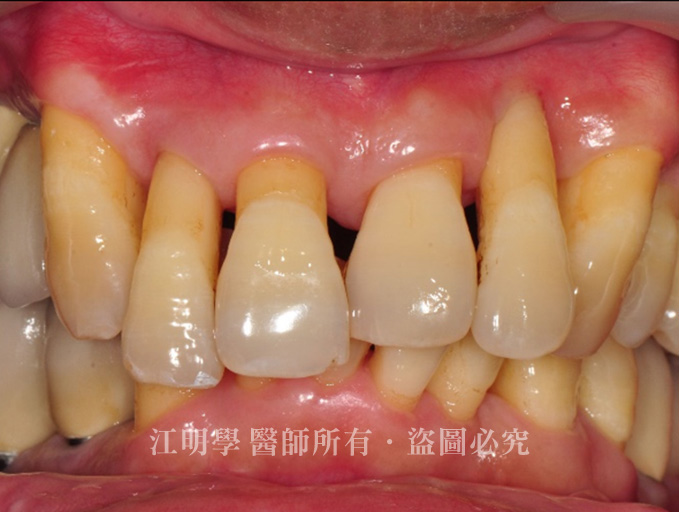

門牙的牙周病造成的牙齒長短不一

治療前